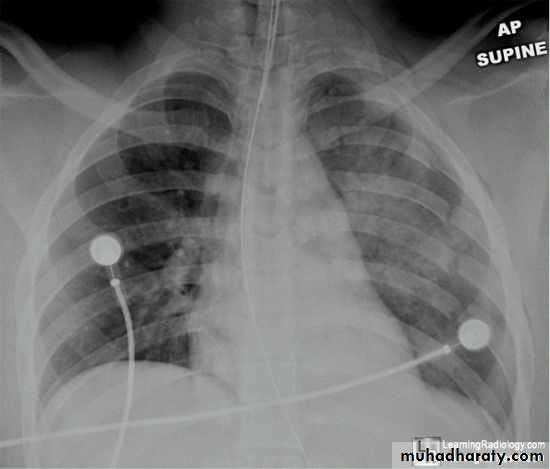

Severe dyspnea with shock

Tension PneumothoraxTension Pneumothorax

!! pneumothorax

pneumothorax